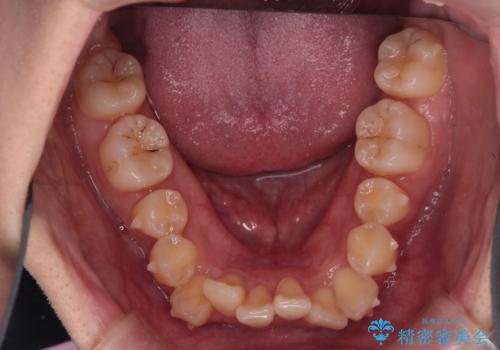

反対咬合を治したい。インビザライン

- 前歯の反対咬合を治したいことを主訴に来院されました。

インビザラインにて臼歯の遠心移動を行いながら、スペースを作り反対咬合を改善することができました。